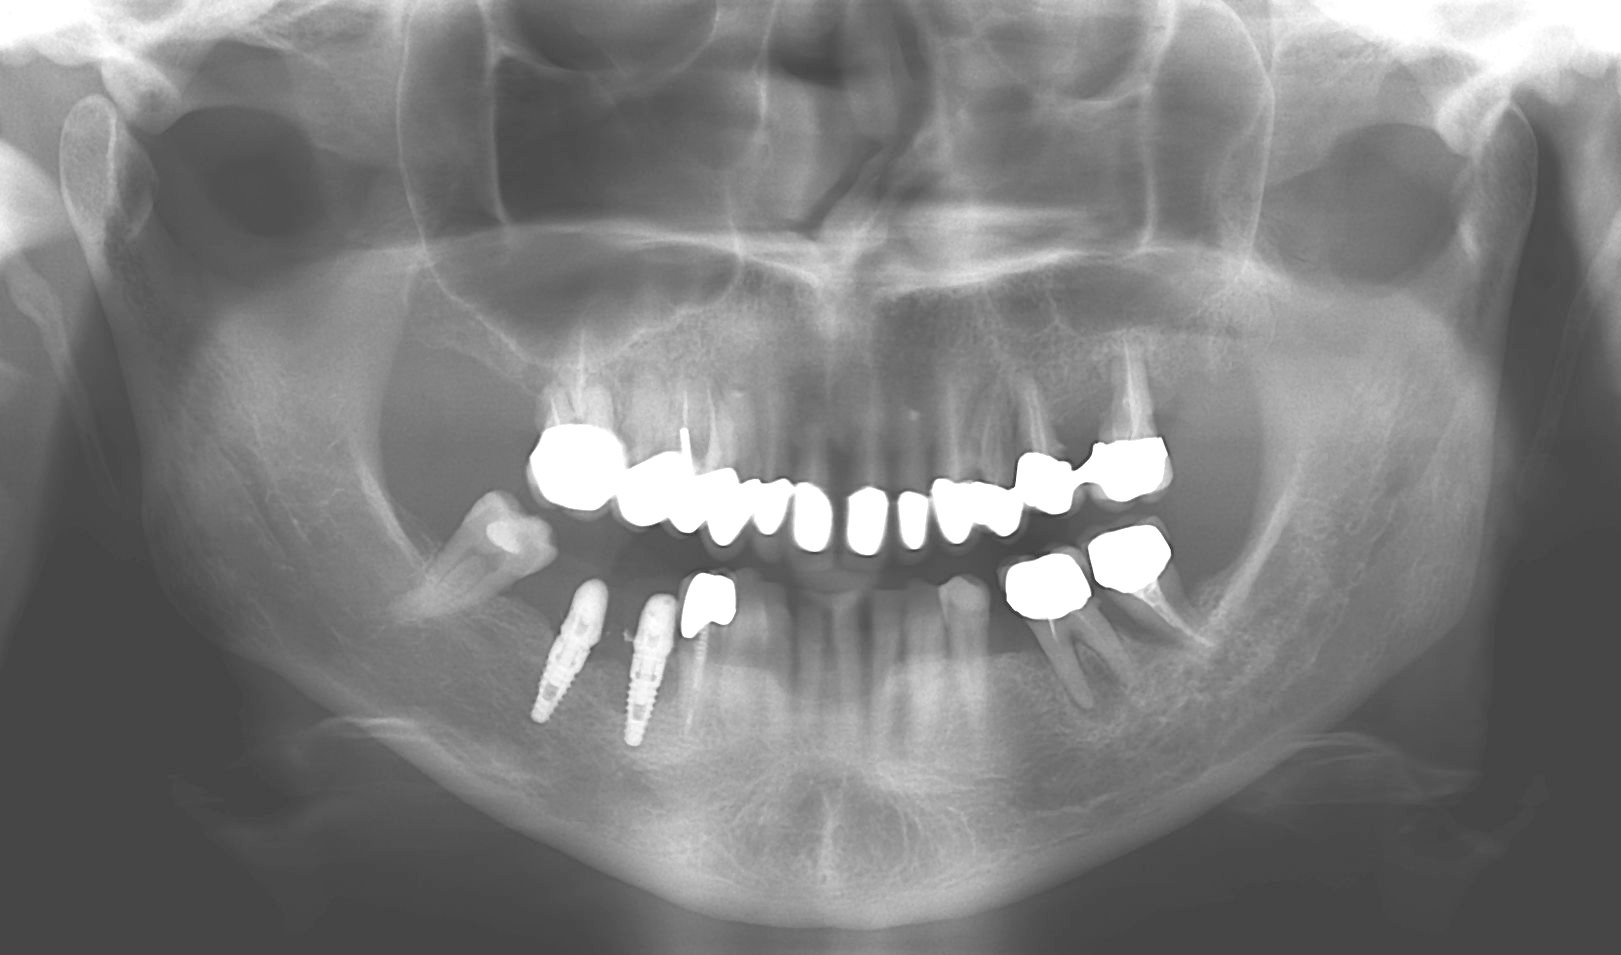

Caso 2

Il paziente, quando era ancora bambino, ha subito un trauma sull’incisivo centrale provocandone la necrosi e interrompendo la crescita completa della radice. Il dente è stato curato e riabilitato in modo tale da mantenerlo in arcata per più tempo possibile. A crescita completa del paziente, a causa dello stato precario dell’elemento dentario, si è proceduto con la sostituzione con un impianto osteointegrato.

PRIMA